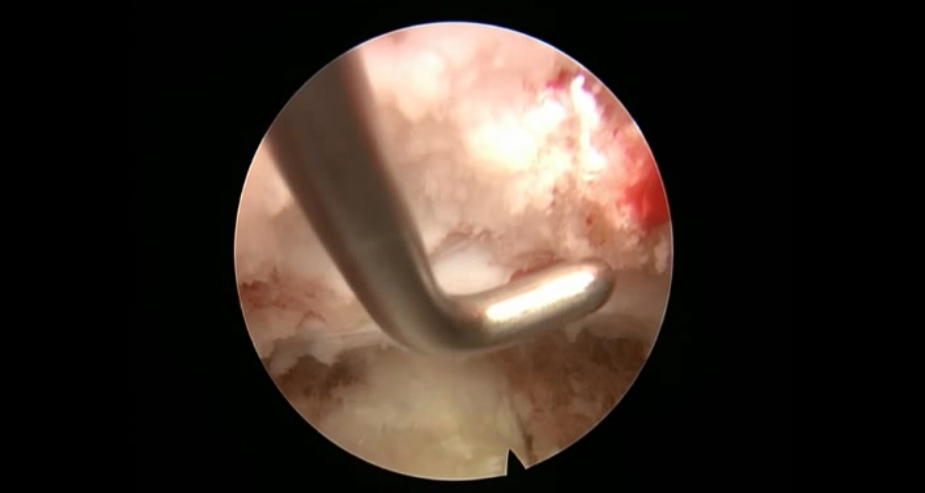

点击以上图片,查看术中视频(超链接:http://res.orthonline.com.cn/video/case5---20.mp4)